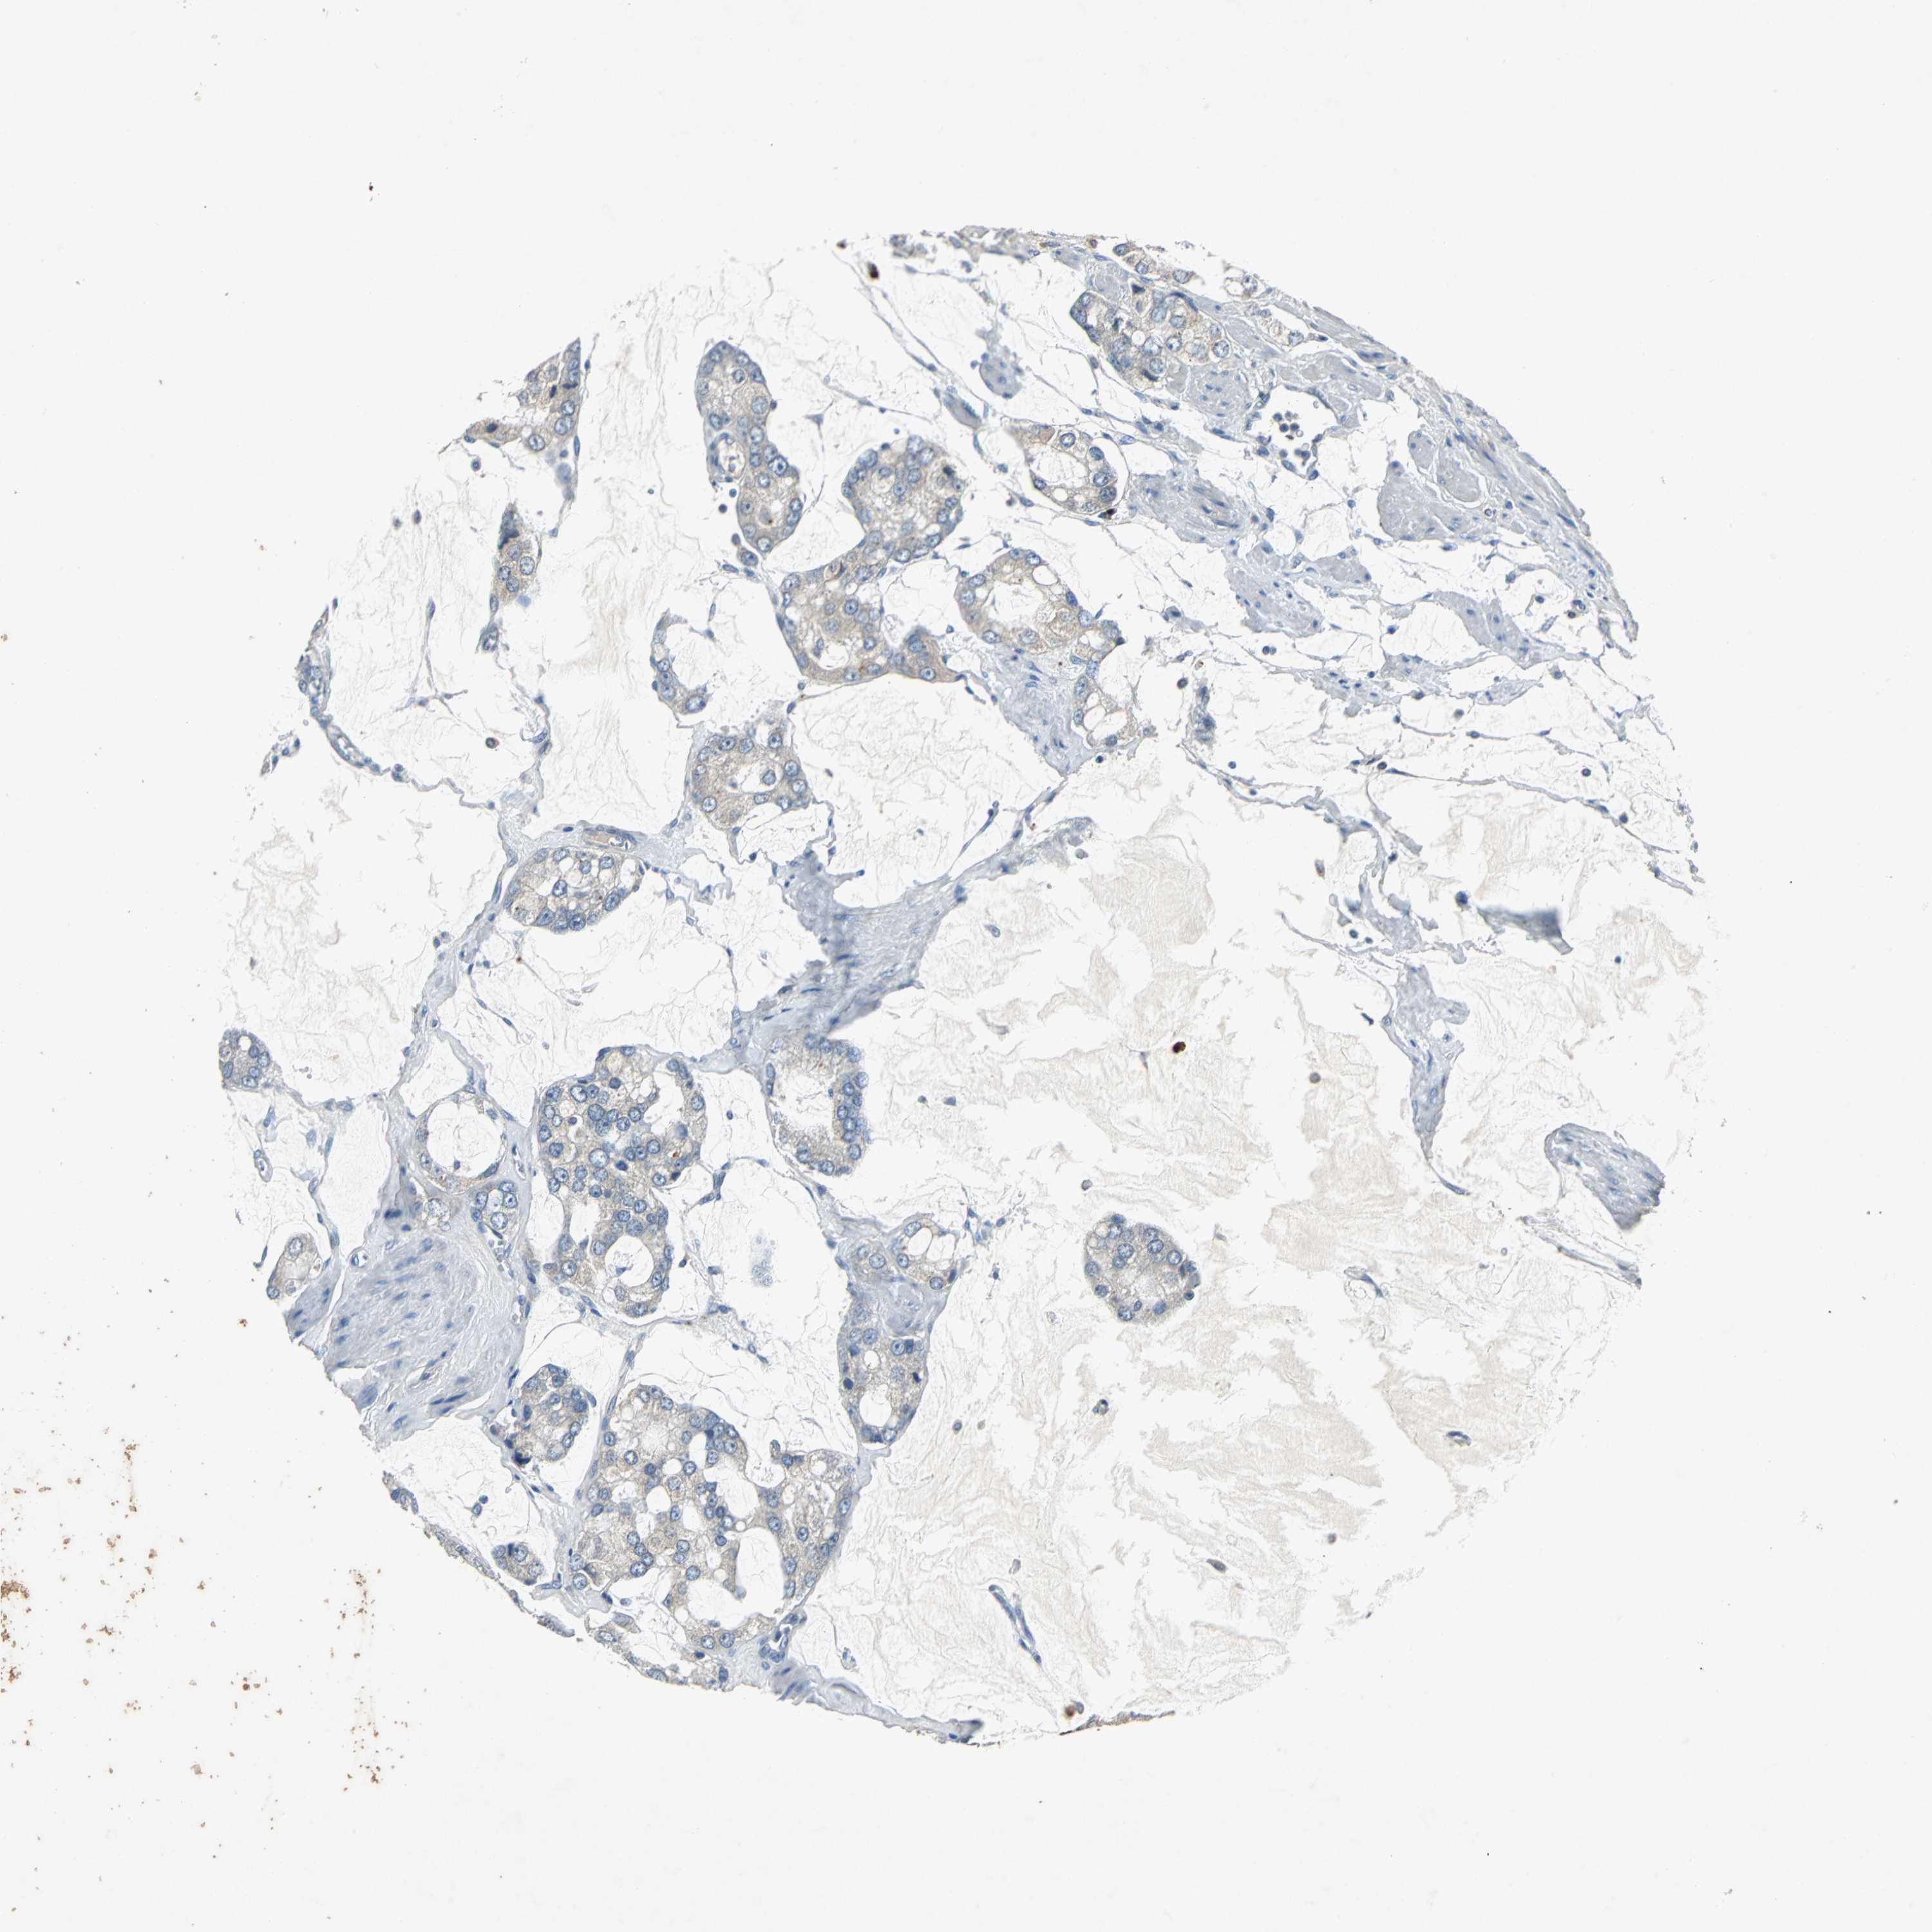

PROSTATE CANCER - Protein expressioni

A mouse-over function shows sample information and annotation data. Click on an image to view it in a full screen mode. Samples can be filtered based on level of antibody staining by selecting one or several of the following categories: high, medium, low and not detected. The assay and annotation is described here.

Note that samples used for immunohistochemistry by the Human Protein Atlas do not correspond to samples in the TCGA dataset.

Antibody stainingi

Antibody staining in the annotated cell types in the current human tissue is reported as not detected, low, medium, or high, based on conventional immunohistochemistry profiling in selected tissues. This score is based on the combination of the staining intensity and fraction of stained cells.

Each image is clickable and will lead to virtual microscopy that enables deeper exploration of all samples and also displays staining intensity scores, fraction scores and subcellular localization as well as patient and tissue information for each sample.

Antibody HPA006584

Antibody HPA061679

Staining

High

Medium

Low

Not detected

Intensity

Strong

Moderate

Weak

Negative

Quantity

>75%

75%-25%

<25%

None

Location

Nuclear

Cytoplasmic/membranous

Cytoplasmic/membranous,nuclear

Adenocarcinoma, Low grade

Adenocarcinoma, High grade

Adenocarcinoma, NOS